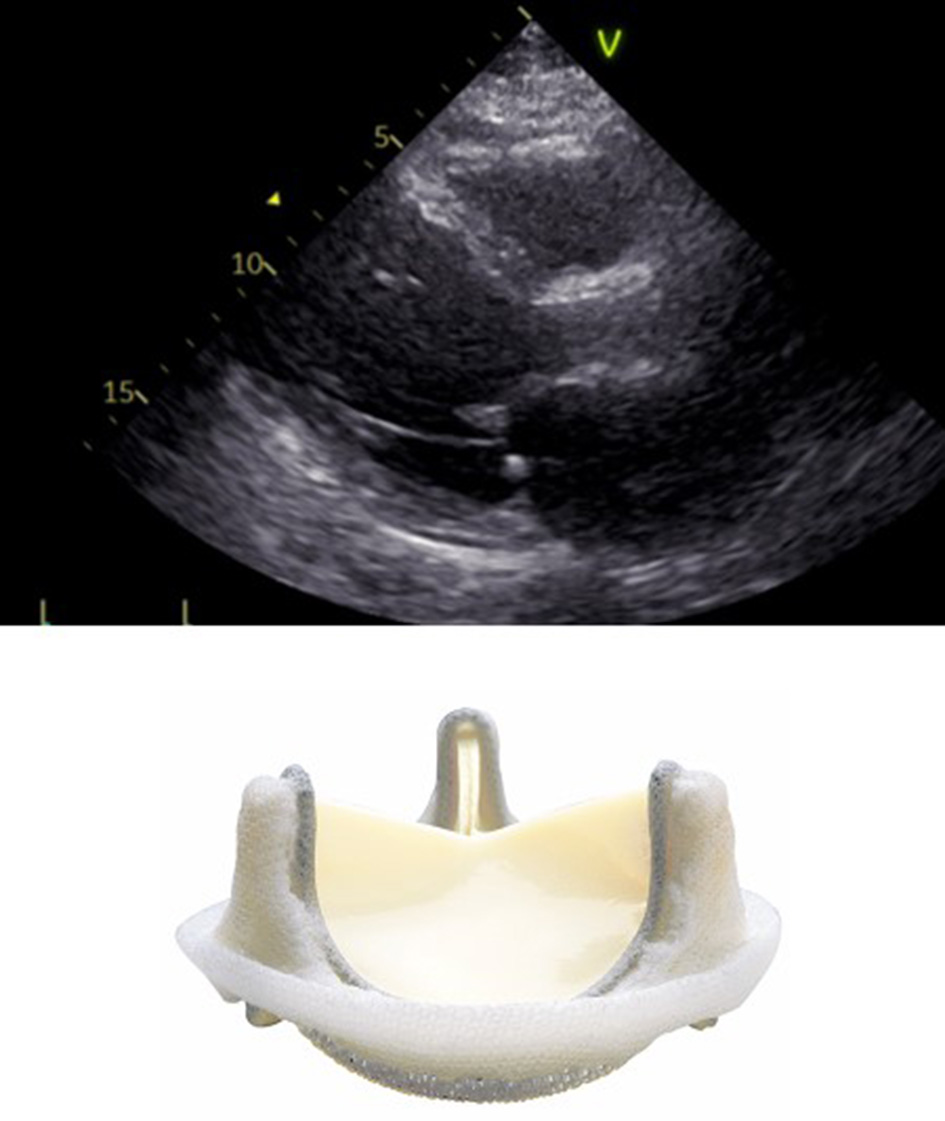

In surgical prostheses, there is only one area of flow acceleration within the suture ring. The LVOT should be measured outer-to outer edge at the inferior edge of the suture ring with the pulse wave Doppler sample positioned at the same level (Figure 2).

FIGURE 2

www.frontiersin.org

Figure 2. Correct measurement of LVOT diameter below the inferior edge of the suture ring as indicated by the yellow bar in a surgical bioprosthetic valve (Perimount 2900).